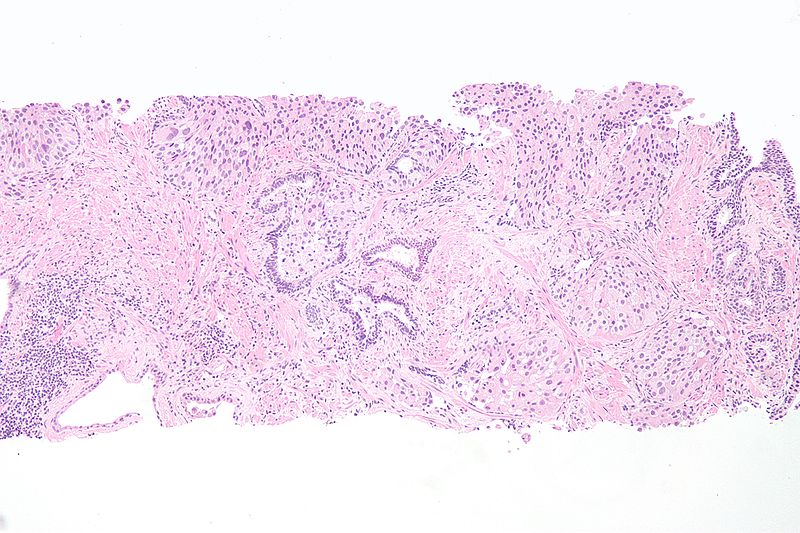

Urothelial Carcinoma

Urothelial carcinoma is also known as transitional cell carcinoma.

The epithelial lining of the renal pelvis, ureter, bladder, or urethra is the source of this malignant tumor.

Urothelial carcinoma is the most typical type of bladder cancer.

Urothelial carcinoma arises via two distinct pathways:

- Flat

- Papillary

Flat urothelial carcinoma is characterized by the invasion of a high-grade flat tumor and is associated with p53 early mutations.

Papillary urothelial carcinoma initially appears as a low-grade papillary tumor, advances to a high-grade papillary tumor, then invades, and is not linked to early p53 mutations.

A field defect is when a tumor recurs and is frequently multifocal in nature.